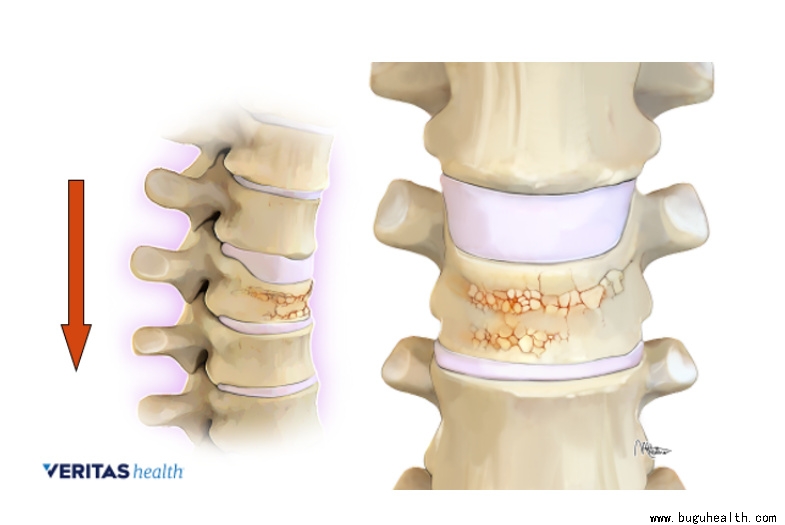

骨质疏松性椎体压缩骨折,英文全称为Osteoporotic Vertebral Compression Fractures,简称为OVCFs,是指由于原发性骨质疏松症导致脊柱椎体骨强度减低,骨质量下降,脆性增加,进而使得脊柱在轻微外力甚至没有明显外伤的情况下,就出现脊柱椎体的压缩性骨折。

骨质疏松的骨质,就好像木质建筑被蛀虫啃食得千疮百孔,强度降低自然更容易断裂。由于脊柱主要承受着躯干的重量,受重力作用向下传递,因此最常见的骨折类型就是压缩性骨折。表现为椎体前柱的塌陷,后柱相对完整,可引起局部的后凸。